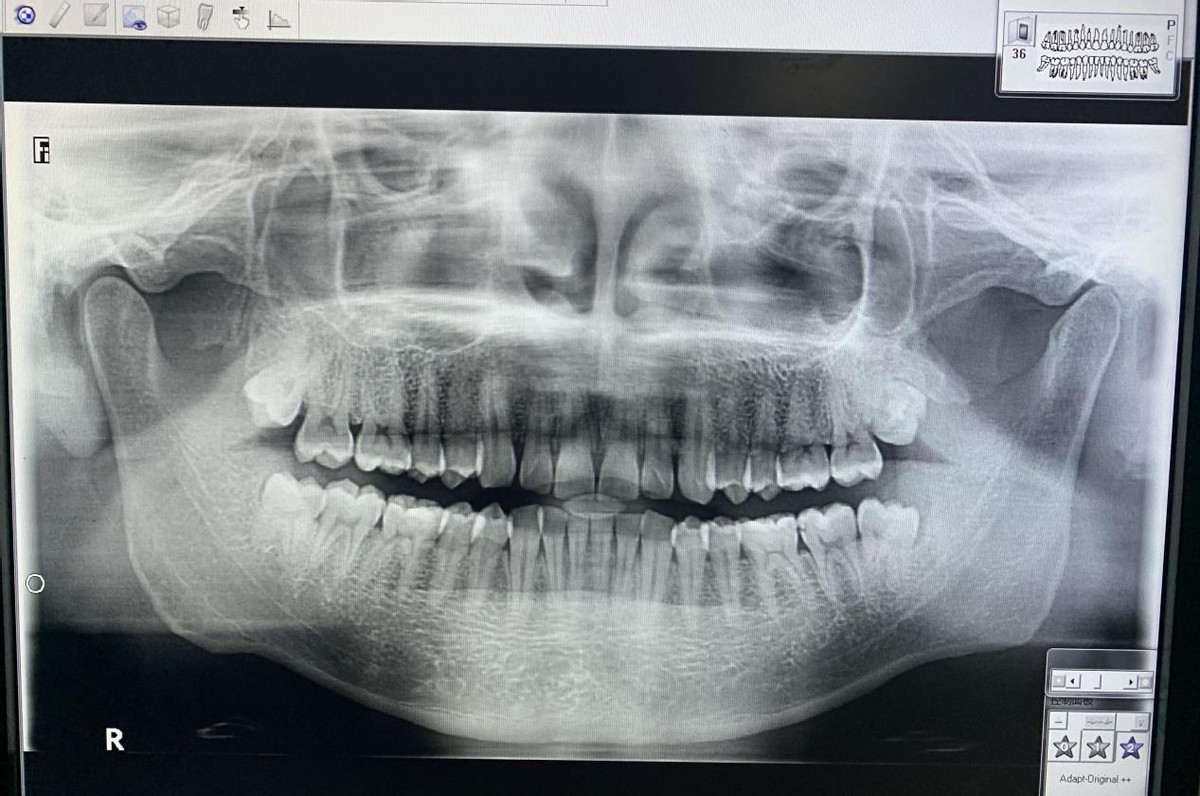

没错这就是我的牙齿!一个月前,右下方智齿萌出的位置发炎了,然后去口腔科拍了个片子,发现我有四颗智齿,上面的两颗都没有萌出,左下方的智齿也没有任何不适,建议先拔右下方的这颗!